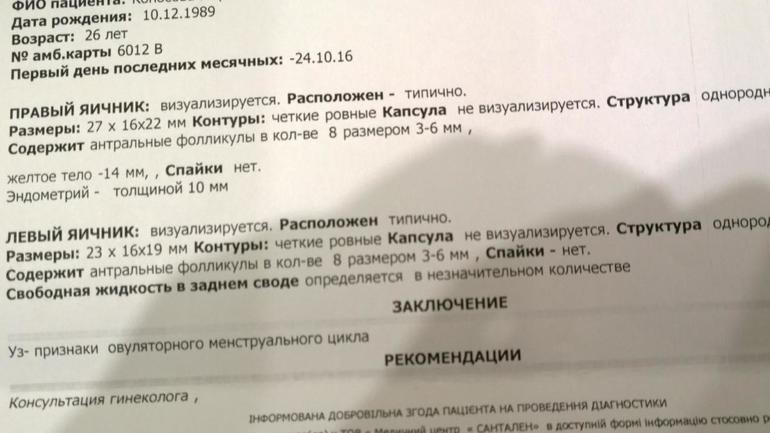

Девочки, помогите разобраться, пожалуйста. Сегодня была на узи. Вчера была О. Эндометрий 10мм.

Узистка написала, что желтое тело 14 мм. Но на первом фото размеры 18.9*16.1*22.6 мм.

На втором фото 14.2*22.3*16.4*26.9.

Правильно она написала? На втором фото желтое тело и оно 14 мм??? такое маленькое...(((

снизу подписала она фото, но я не понимаю ее почерк (